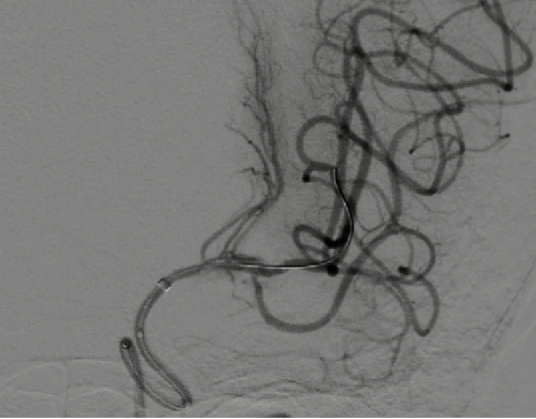

支架释放后影像。

导丝怎么扩【载药时代 球扩天下】NOVA DES®颅内药物洗脱支架在颅内富穿支区域使用体会二例!_https://www.jmylbn.com_新闻资讯_第32张

导丝怎么扩【载药时代 球扩天下】NOVA DES®颅内药物洗脱支架在颅内富穿支区域使用体会二例!_https://www.jmylbn.com_新闻资讯_第33张

导丝怎么扩【载药时代 球扩天下】NOVA DES®颅内药物洗脱支架在颅内富穿支区域使用体会二例!_https://www.jmylbn.com_新闻资讯_第34张

术后影像及检查

影像结论:狭窄解除。

支架位置良好,狭窄解除。